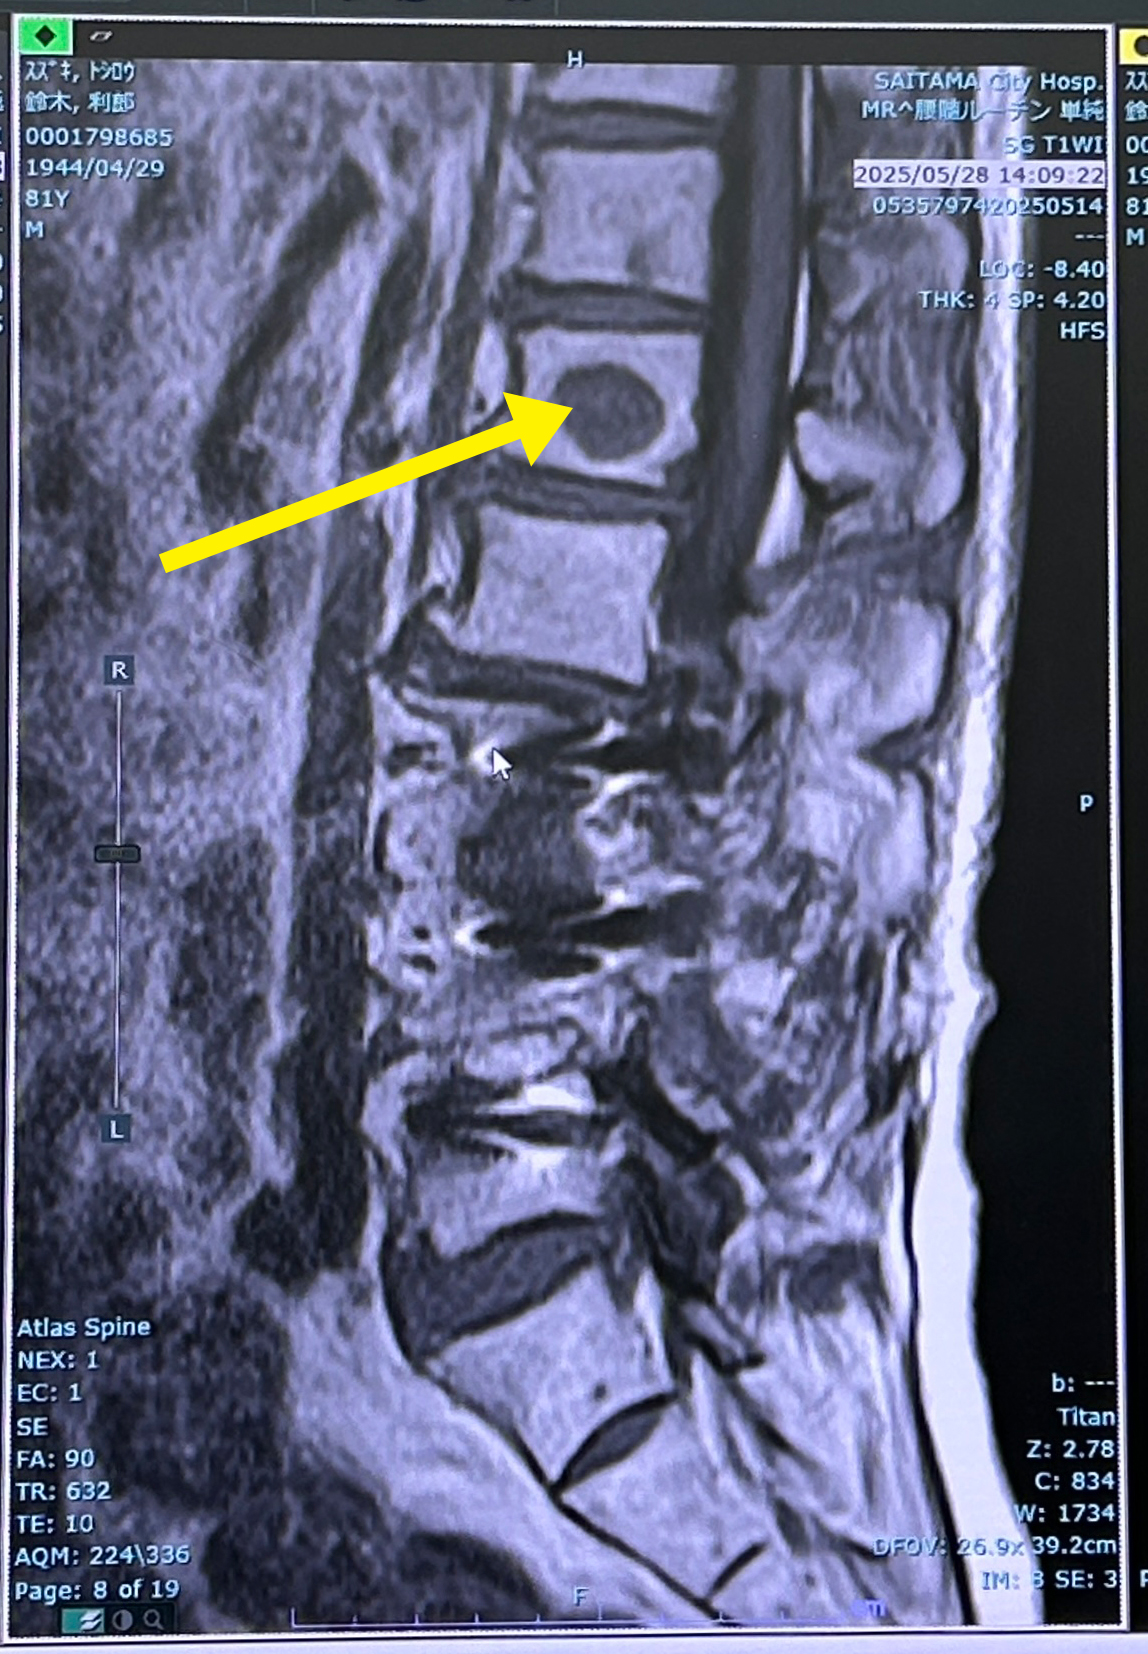

肝心の胸周辺の痛みは、胸周辺のMRIから、脊髄の癌が胸の痛みに起因してういると、説明。

脊髄のMRIでがんが転移した部分は黒くなっている。

放射線治療を24,25日に実施するようになった。